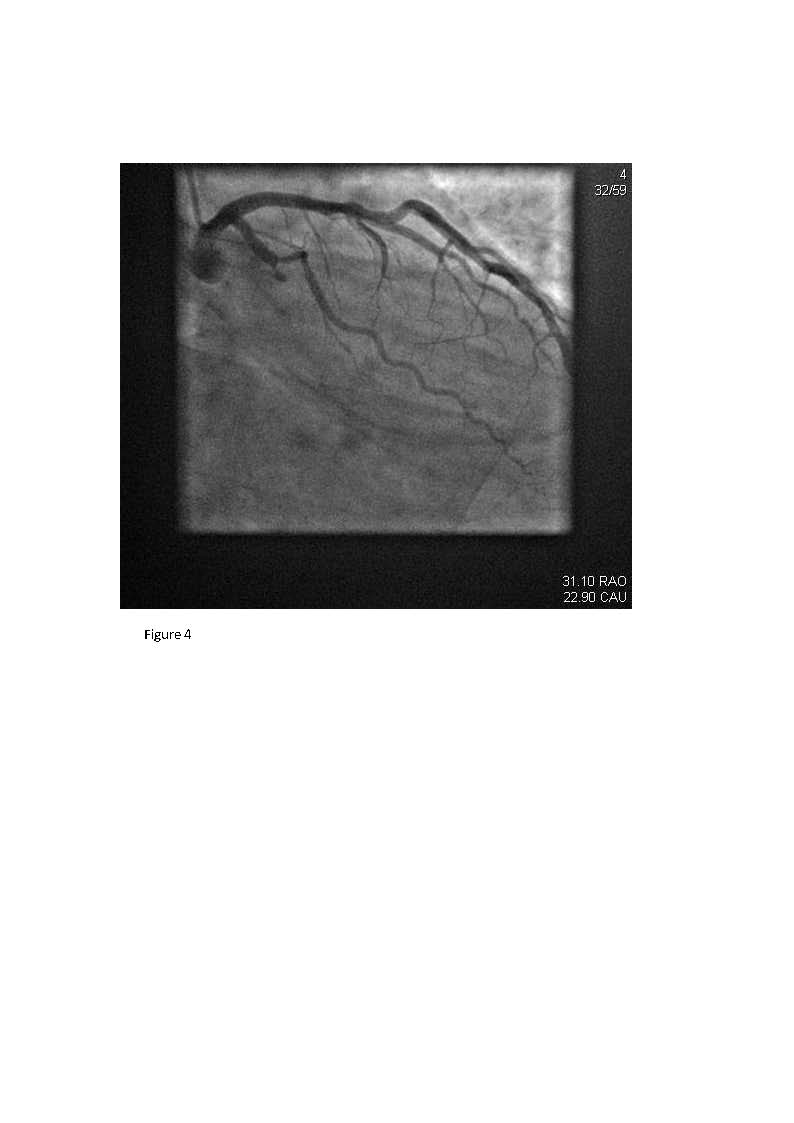

We report the case of a 50-year-old man with history of hypertension who presented with chest pain and subtle electrocardiographic (ECG) abnormalities. Only with the aid of additional high lateral and posterior ECG leads (V7-9) was a posterolateral acute myocardial infarction identified and subsequently confirmed with positive cardiac enzyme serology. Coronary angiography showed total occlusion of the left circumflex coronary artery, which was successfully recanalized via coronary angioplasty and stenting. This case highlights the use of high lateral and posterior ECG leads (15-lead ECG) in enhancing the diagnostic yield of a conventional ECG in patients presenting with symptoms suspicious for an acute coronary syndrome by disclosing a posterior myocardial infarction and guiding reperfusion therapy.